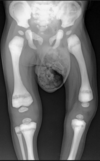

3 radiographic findings in osteopetrosis

Rugger jersey spine

Erlenmeyer flask distal femur

Thickened cortex/lack of a IM canal